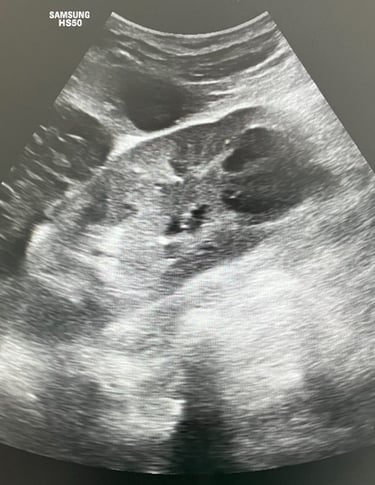

Apendicită acută - aspect ecografic sugestiv